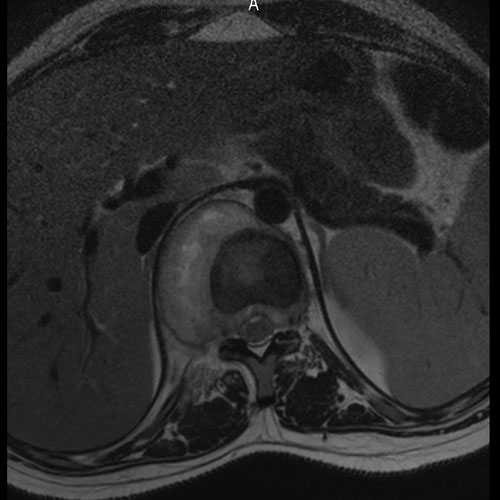

28 year old female with left lower abdomen pain. MRI showing torsion of Fallopian tube.